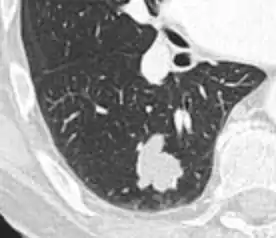

- Location: Upper lobe location is a risk factor for cancer, while a location close to a fissure or the pleura indicates a benign lymph node,[8] especially if having a triangular shape.[9]

- Margin morphology: a spiculated margin is a risk factor for cancer.[8] Benign causes tend to have a well defined border, whereas lobulated lesions or those with an irregular margin extending into the neighbouring tissue tend to be malignant.[10] In particular, spiculations are highly predictive of malignancy with a positive predictive value up to 90%.[9] Also, a "notch sign", which is an abrupt indentation of the nodule, increases the risk of cancer, but may also be found in granulomatous diseases.[9]

Spiculated lung nodule.[9]